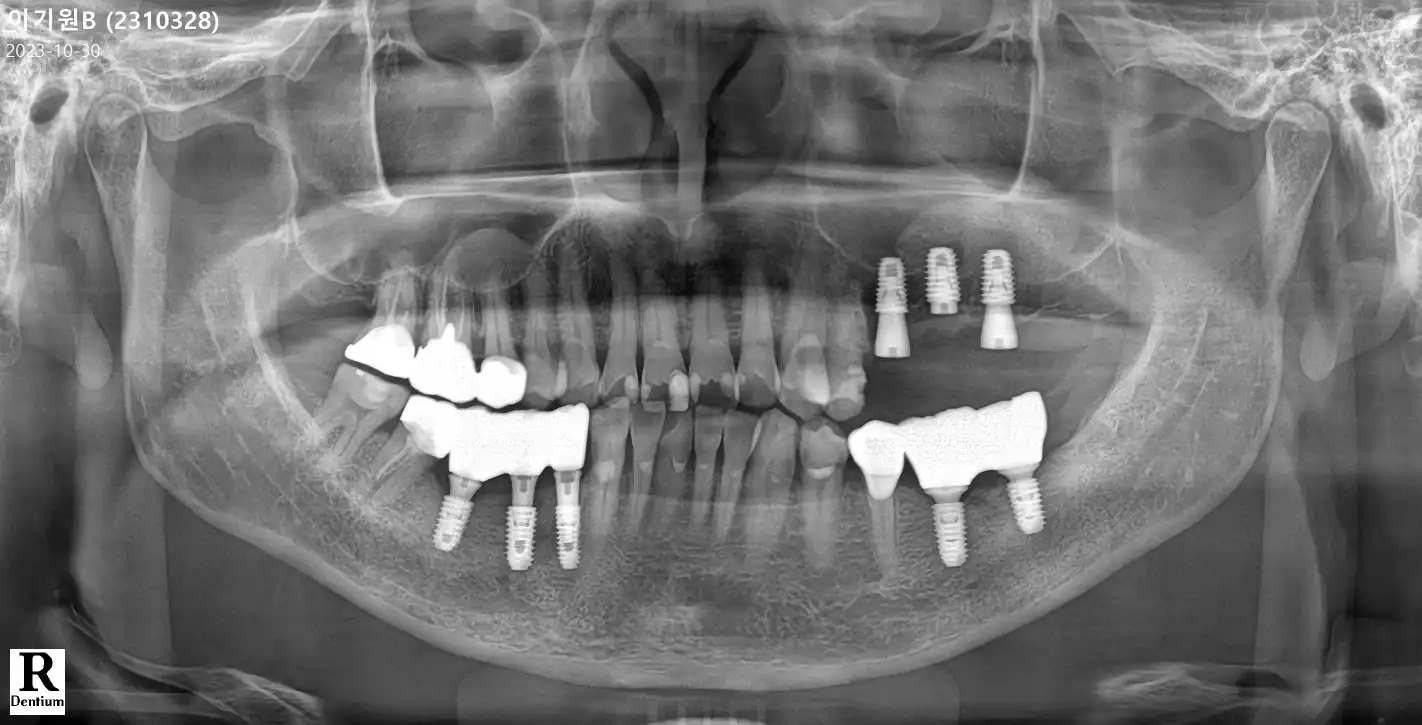

전

후

임플란트 상담 받고 바로 수술 했어요 상담사분들 친절하시구요 이가 많이 안좋아진 상태여서 남편이랑 같이 임플란트 수술 결정 했어요 사람이 많아서 대기시간이 많이 있었지만 수술은 그리 많이 걸리진안았어요 임플란트가 무서워서 너무 늦춰져서 이를 많이 빼야 해서 불편하지만 그래도 후기들많고 많이 찾아오셔서 믿고 했습니다